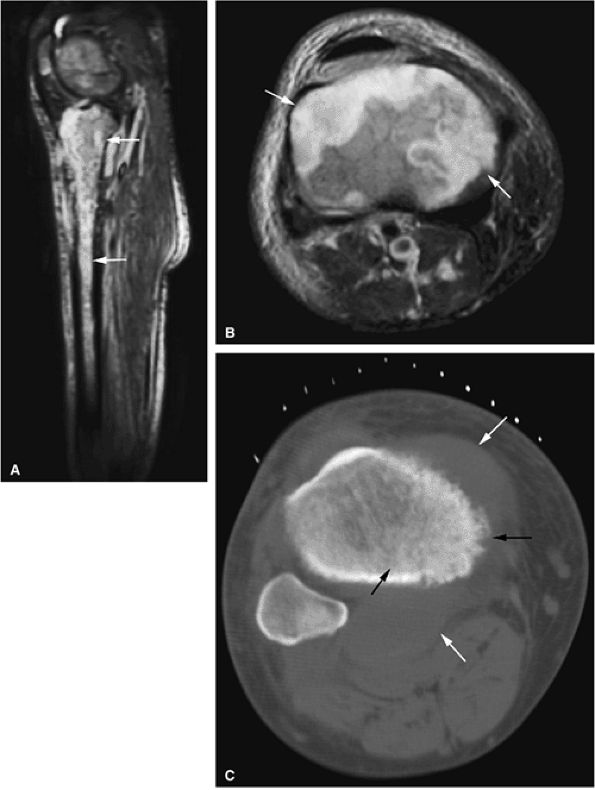

FIGURE 13.31 ● High-grade lymphoma of bone. (A) Marrow involvement of the distal femur is hypointense on a coronal T1-weighted image (arrows). (B) The extent of marrow involvement is better seen on a sagittal STIR image (white arrows). Peritumoral edema and soft-tissue component are hyperintense (black arrowheads). (C) Large associated soft-tissue component is seen on an axial fat-suppressed T2-weighted image (arrows). (D) Axial CT image obtained for biopsy shows destruction of the distal femur with pathological fracture (arrow). (E) Osseous destruction with soft-tissue component is demonstrated (arrows).

|